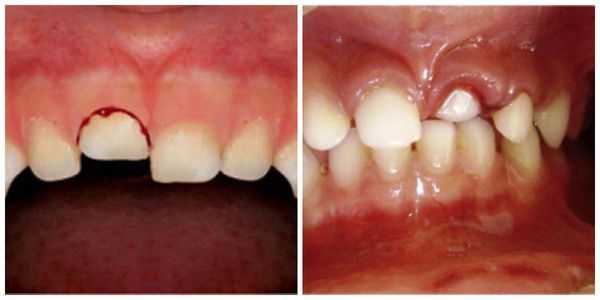

Вколоченный вывих зуба (интрузия) сопровождается внедрением корня зуба в толщу кости альвеолярного отростка и погружением коронковой части зуба в лунку. При таком виде травмы коронка становится короче окружающих зубов, возникают боли, луночное кровотечение.

- Вколоченный вывих : пациент чувствует постоянную боль, усиливающуюся при давлении, жевании, смыкании челюстей; при пальпации десны появляется её гиперемия (покраснение) и отёчность; возникает незначительное кровотечение из места травмы. Что интересно, при перкуссии (постукивании) травмированного зуба человек не ощущает болевых ощущений и дискомфорта. При визуальном осмотре заметно укорочение зуба или же он полностью "спрятан" в лунке, при этом неподвижен.

Вколоченный вывих — это травма считается наиболее неблагоприятной. Тело зуба под воздействием большой давящей силы погружается в ткани челюсти (он входит глубоко в лунку) и корень внедряется вглубь альвеолярного отростка и тела челюсти. Для вколоченного вывиха также характерен полный разрыв волокон периодонта. Крайне редко некоторая их часть сохраняет свою непрерывность, но существенно растягивается и надрывается. Сосудисто-нервный пучок, как правило, разрывается. Из-за внедрения более широкой части зуба в более узкую происходит деформация стенок альвеолы: они раздвигаются и ломаются. Данный вид вывиха иногда сопровождается поворотом зуба вокруг оси, смещением в вестибулярном или оральном направлении. Особенно это касается верхних зубов, когда вследствие вывиха может произойти повреждение носовых (гайморовых) пазух.